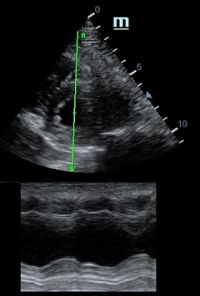

Но как же провести стандартные измерения в М-режиме, если мы его не использовали? На помощь приходит функция Free Xros M – анатомический М-режим. Имея записанную в память прибора видео петлю, мы можем провести линию М-режима в любом месте, при этом корректируя изначально не оптимальный угол.

Возможности применения функции многогранны: от измерения толщины стенок левого желудочка, движения створок митрального клапана и кооптации нижней полой вены до оценки сократимости миокарда как глобально, так и по сегментам.

TAPSE - показатель амплитуды движения латеральной части кольца трикуспидального клапана, позволяет количественно и быстро оценить систолическую функцию правого желудочка, норма которого составляет более 17 мм. Главным условием является проведение линии М-режима параллельно стенке правого желудочка в апикальном четырех камерном сечении, что легко достигается при Free Xros.

MAPSE - амплитуда движения латерального кольца митрального клапана, позволяет рассчитать фракцию выброса по формуле EF = 4.8 × MAPSE (mm) + 5.8, очень быстрый и гораздо более точный («прародитель Strain») метод чем широко распространенный метод Teicholtz. В современных приборах можно легко добавить свою формулу при отсутствии ее в стандартном калькуляторе. Главным условием является проведение линии М-режима параллельно стенке левого желудочка в апикальном четырехкамерном сечении, что легко достигается при использовании функции Free Xros.